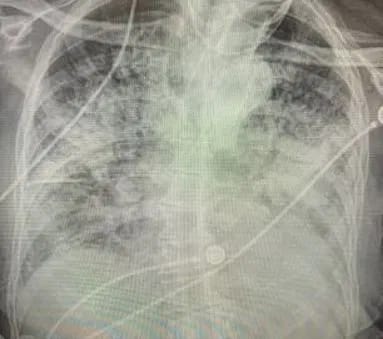

A long X-ray showing the damage done by coronavirus Credit: Dr Brittany Bankhead-Kendall

One image shows a normal healthy pair of lungs, another the lungs of a smoker, and the third the lungs of a coronavirus patient.The normal lungs are dark and see-through, the smoker’s are partly whited by scarring, while the coronavirus patient’s are in parts almost opaque.

Writing on twitter, Dr Bankhead-Kendall said: “I don’t know who needs to hear this, but ‘post-Covid’ lungs look worse than any type of terrible smoker’s lungs we’ve ever seen.

“And they collapse. And they clot off. And the shortness of breath lingers on… & on… & on.”